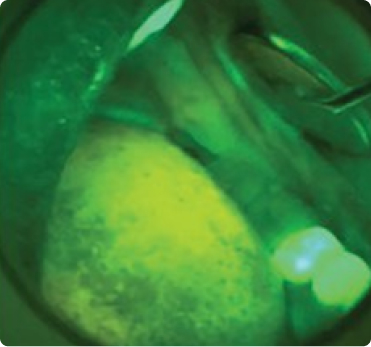

White Light Examination

Under VELscope

Bacterial infections appear red

Yeast infections appear yellow/orang

Porphyrins, byproducts of bacterial metabolism, absorb the VELscope’s blue light and re-emit it as red autofluorescence.​

Yeast cells contain molecules that fluoresce yellow or yellow-orange under VELscope